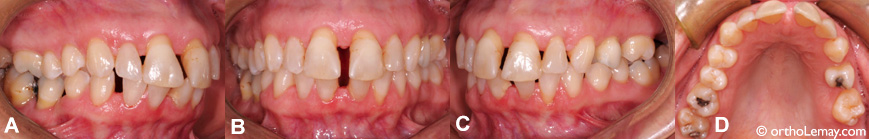

Tous ces cas ont une absence héréditaire des 2 latérales supérieures ce qui permet aux dents adjacentes de se déplacer et de créer ainsi des espaces interdentaires. Parfois, il ne manque qu’une seule latérale et l’autre latérale présente est souvent de dimension réduite (étroite).

• (A à D) Chez cette femme de 49 ans, le niveau osseux supportant les dents a diminué avec les années (problèmes parodontaux). Les dents étant moins bien supportées ne résistent pas autant aux forces appliquées contre elles provenant de la fonction normale (mastication) et de la langue qui s’appuie contre les dents. Ceci peut permettre des espaces de se développer progressivement même si cela peut prendre des années voire des décennies.